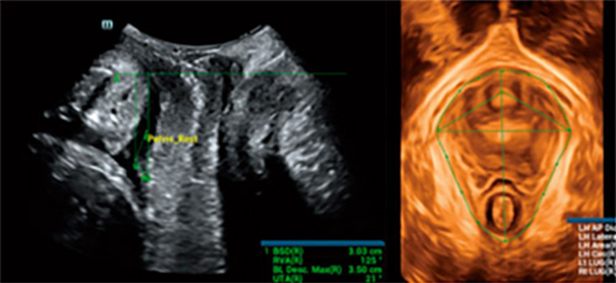

Om echografisten te helpen snel gestandaardiseerde secties en metingen te verkrijgen bij complexe bekkenbodemonderzoeken en de diagnostische effici?ntie te verbeteren, heeft Mindray Smart Pelvic ontwikkeld, een slimme oplossing voor echografie van de bekkenbodem. Deze oplossing kan automatisch volledige bekkenmetingen verrichten en automatische 3D-beeldvorming bieden van de levator hiatus, samen met metingen van de longitudinale diameter, de transversale diameter, het levator hiatus-gebied, en de grootte van de urethra-opening van de levator. Echografisten kunnen uitgebreide klinische gegevens krijgen voor een nauwkeurige beoordeling via een paar eenvoudige interacties, die slechts een derde van de tijd van traditionele onderzoeken in beslag nemen. Daarnaast biedt Mindray drie primaire industri?le standaarden die verschillende soorten sondes ondersteunen en een gestandaardiseerde werking mogelijk maken.

Smart Pelvic